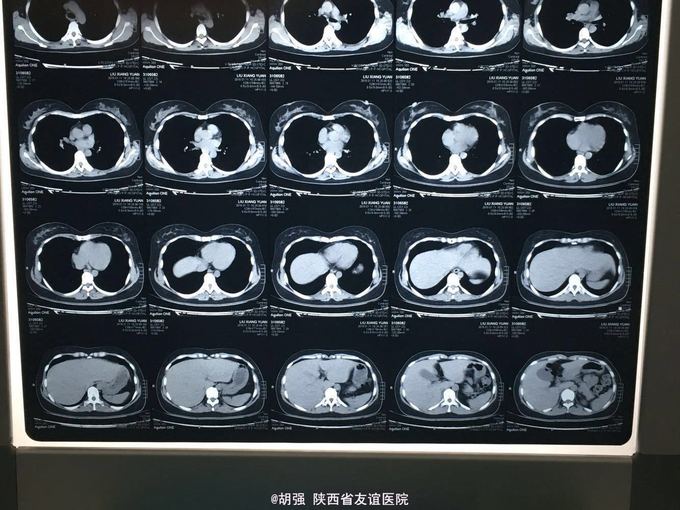

32岁女性患者,咳嗽、咳痰2周余 患者于两周前不明诱因出现咳嗽、咳痰,无胸痛咯血,无胸闷气短,无发热、寒战,自己服用头孢克肟1.0 2次/日及复方甘草合剂10ml3次/日治疗1周,效果不佳,遂来我院。 既往体检。

查体:两肺呼吸音粗糙,未闻及干湿性啰音及胸膜摩擦音。余查体无明显异常。 入院后查胸部CT无明显异常。血常规、肝肾功、血沉、结核抗体、心电图大致正常。T-sport试验及PPD试验 阴性。支气管镜检查:右肺中叶可见大量脓痰,吸痰送检。痰培养回报:肺炎链球菌。